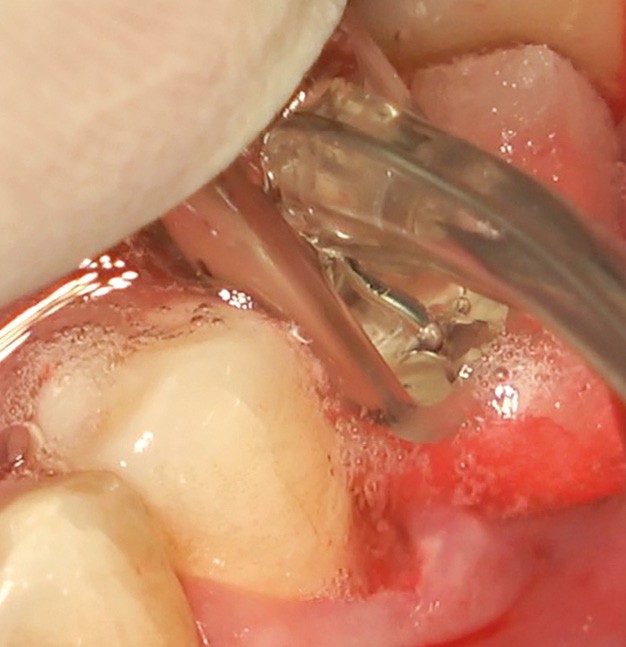

Chez ce patient, le traitement de la péri-implantite a comporté une chirurgie associant décontamination électrolytique de la surface implantaire, régénération osseuse guidée et enfouissement de l’implant. Le résultat à 2 ans est très moyen au vu du pourcentage de régénération osseuse obtenu. Comment peut-on prévoir un tel résultat alors que l’on a suivi les recommandations à la lettre, que l’on a utilisé les dernières technologies de décontamination, que l’on y a mis tous les moyens, que le patient est en bonne santé générale et qu’il vient en plus régulièrement aux séances de thérapeutique de soutien ? Le succès du traitement des péri-implantites n’est pas simple à obtenir, surtout quand un élément clé est compromis… la maintenance personnelle ! En effet le succès n’est possible que si le contrôle de plaque quotidien est optimal et, ici, ça n’était pas le cas. Le patient se brossait certes les dents, mais ne passait pas quotidiennement les brossettes, ce qui…